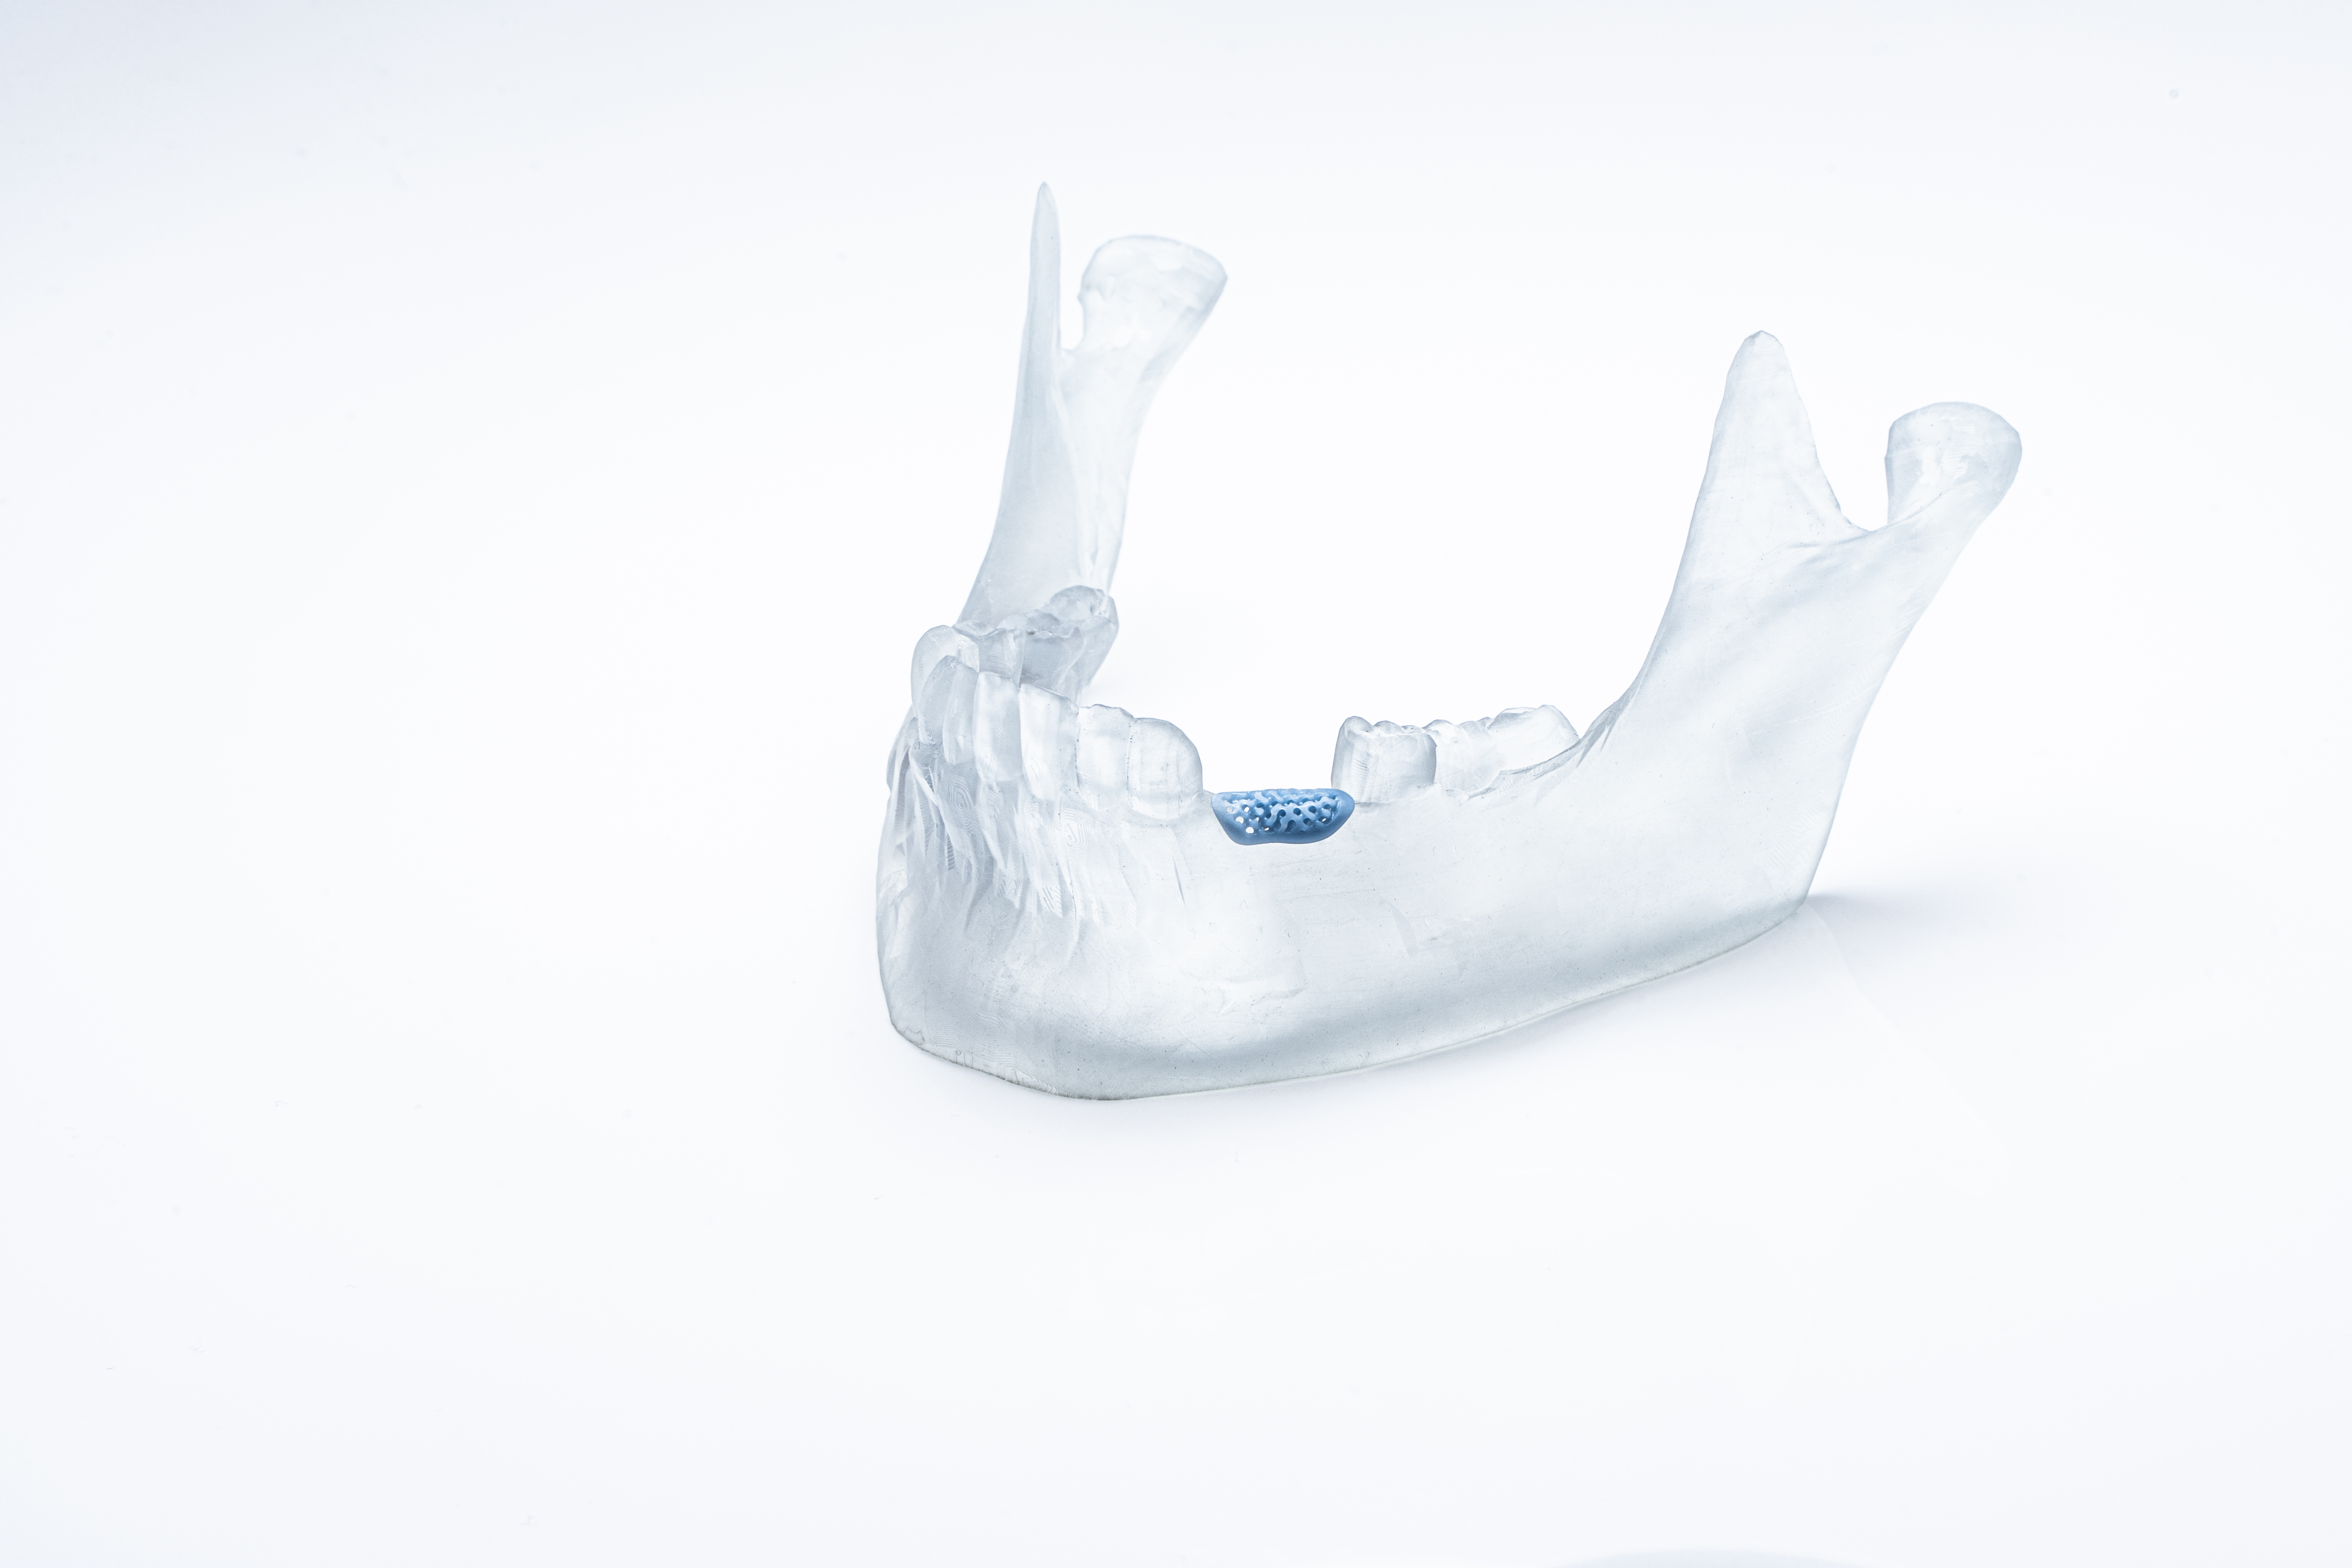

● Further innovations shown feature a bioresorbable hydroxy apatite jawbone and serially 3D-printed dental implants made of zirconia (TZP-A) or aluminatoughened zirconia (ATZ)

Further ground-breaking dental applications made possible by the impressive precision of LCM technology and on display at IDS include a bioresorbable jawbone (hydroxy apatite or tricalcium phosphate) and additively serially manufactured dental implants made of zirconia (TZP-A) or alumina-toughened zirconia (ATZ).